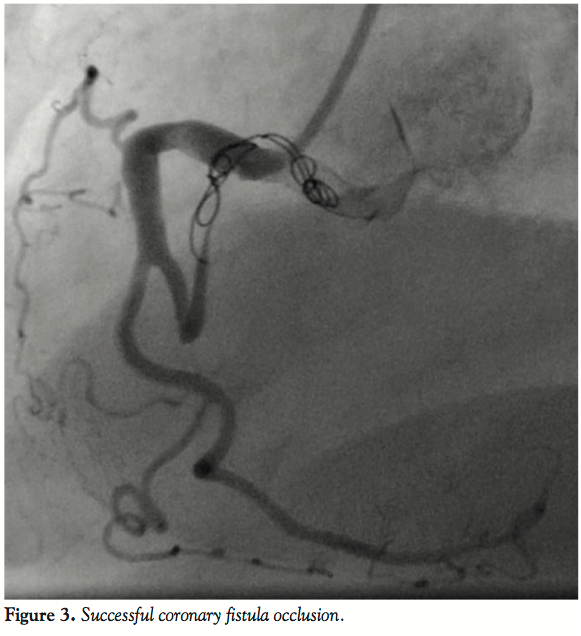

A coronary angiogram showed no signs of atherosclerotic coronary artery disease. However, it revealed a voluminous fistula between the proximal segment of the right coronary artery and a branch of the pulmonary artery. Without other plausible causes for her condition, the patient was subsequently called for percutaneous closure of the coronary fistula, which was successfully performed using 3 AZUR embolization coils (platinum coils coated with hydrocolloid gel). Figures 1-3 show the coronary fistula before, during, and after the procedure. One month later, she is asymptomatic.